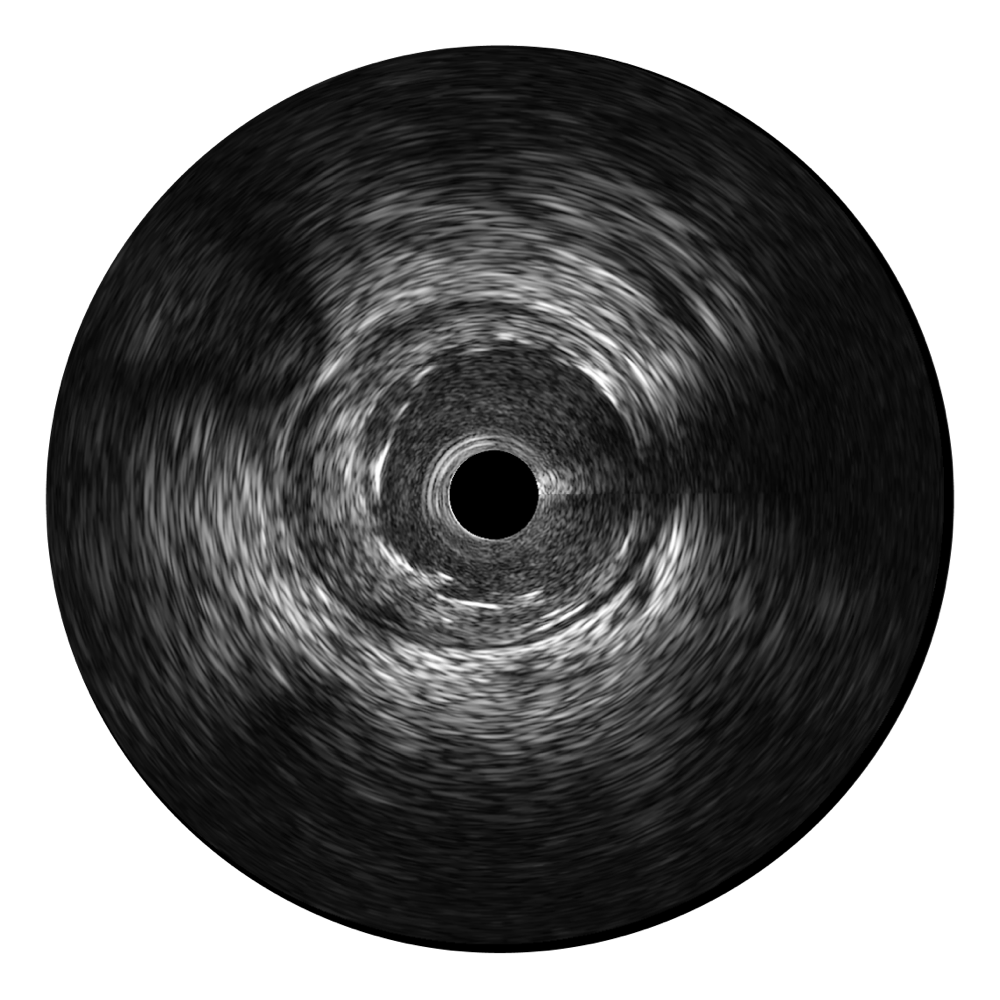

球速体育入口宽频IVUS图像

对比传统IVUS导管成像,球速体育入口宽频IVUS图像的近场支架梁显影更细腻,远场中膜外血管仍清晰可辨,兼顾远中近,兼顾分辨力与穿透深度